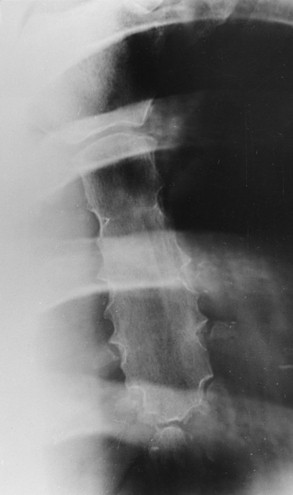

The 12 pairs of ribs are numbered consecutively from superiorly to inferiorly (Fig. 9-4; see Figs. 9-1 and 9-2). The rib number corresponds to the thoracic vertebra to which it attaches. Each rib is a long, narrow, curved bone with an anteriorly attached piece of hyaline cartilage, the costal cartilage. The costal cartilages of the first through seventh ribs attach directly to the sternum. The costal cartilages of the 8th through 10th ribs attach to the costal cartilage of the 7th rib. The ribs are situated in an oblique plane slanting anteriorly and inferiorly so that their anterior ends lie 3 to 5 inches (7.6 to 12.5 cm) below the level of their vertebral ends. The degree of obliquity gradually increases from the 1st to the 9th rib and then decreases to the 12th rib. The first seven ribs are called true ribs because they attach directly to the sternum. Ribs 8 to 12 are called false ribs because they do not attach directly to the sternum. The last two ribs (11th and 12th ribs) are often called floating ribs because they are attached only to the vertebrae. The spaces between the ribs are referred to as the intercostal spaces.

Ribs vary in breadth and length. The first rib is the shortest and broadest; the breadth gradually decreases to the 12th rib, the narrowest rib. The length increases from the 1st to the 7th rib and then gradually decreases to the 12th rib.